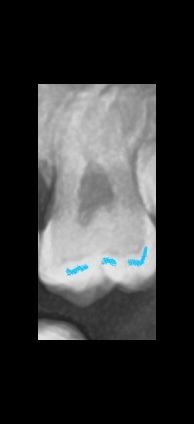

파노라마에 교합면 밑 충치인가요? 어두운 부분

교합면에 약간 충치가있는건가요? 아니면 파노라마찍으면 원래 저렇게 나오는 건가요? ..알려주시면 감사하겠습니다!...

엑스레이 상으로 보이는 저부분은 충치는 아니고 아마 예전에 치료를 한 부분 같습니다. 본딩제가 잇는 부위 같습니다.

방사선 사진만으로는 충치의 여부를 판단하기 힘들어 보입니다.

해당 부위는 충치가 없어도 어두워 보일 수 있는 부분이기 때문에 충치의 여부를 확인하기 위해서는 육안으로의 확인이 필요할 것으로 생각됩니다.